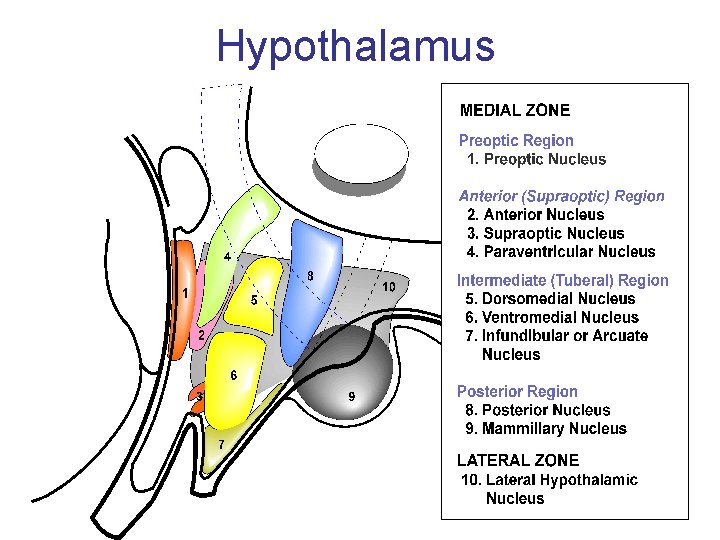

Hypothalamus 3 podélné zóny: periventrikulární, mediální, laterální zóna 3 příčné zóny: přední, střední, zadní hypothalamus Nuclei • přední hypothalamus (area hypothalamica rostralis) - nucleus paraventricularis, supraopticus, suprachiasmaticus • střední hypothalamus (area hypothalamica intermedia et dorsalis) nuclei tuberales laterales et ventromediales • zadní hypothalamus (area hypothalamica posterior) - nuclei mammillares, nucleus h. posterior, nucleus tberomammillaris

Hypothalamus – funkce přijímá podněty z téměř všech receptorů - zejména z RF, prefrontální kůry a hipokampu dřívější názor: • přední hypothalamus - vztah k parasympatiku • střední hypothalamus - vztah k sympatiku • zadní hypothalamus - vztah k limbickému systému

Hypothalamus – funkce Hypothalamus • termoregulace – centrum horečky – přední h. – centrum chladu – zadní h. • • laterální h. : centrum hladu, žízně a zlosti mediální h. : centrum sytosti a pasivity přední h. : centrum spánku a bdělosti sex – ♂ nucleus preopticus – ♀ nucleus ventromedialis

Hypothalamus – funkce Hypothalamus • ncl. suprachiasmaticus – centrum cirkadiálních rytmů • ncl. supraopticus + paraventricularis (magnocelulární neurony) – ADH (vazopresin) + oxytocin • ncl. arcuatus (infundibularis) a okolí (parvocelulární neurony) – statiny a liberiny • ncl. tuberomamillaris – histamin do mozku a míchy („arousal“) • aktivován orexinem z lat. hypothalamu • nedostatek při narkolepsii

Přední hypotalamus • ncl. paraventricularis – oxytocin, ADH • ncl. supraopticus – oxytocin, ADH • ncl. preopticus medialis – pokles tlaku a tepu • ncl. hypothalamicus anterior – termoregulace, pocení, inhibice TSH • ncl. suprachiasmaticus – cirkadiánní rytmus

Střední hypotalamus = tuberální hypothalamus (tuber cinereum) • ncl. infundibularis = ncl. arcuatus – statiny a liberiny • ncll. tuberales – hlad, žízeň • ncl. hypothalamicus ventromedialis – hlad • ncl. hypothalamicus dorsomedialis – zvýšení krevního tlaku a tepu

Zadní hypotalamus • ncll. mammillares – paměť, zapojení do limbického systému (ncl. anterior thalami) • ncll. hypothalamicus posterior – zvyšování tlaku, mydriáza, třes